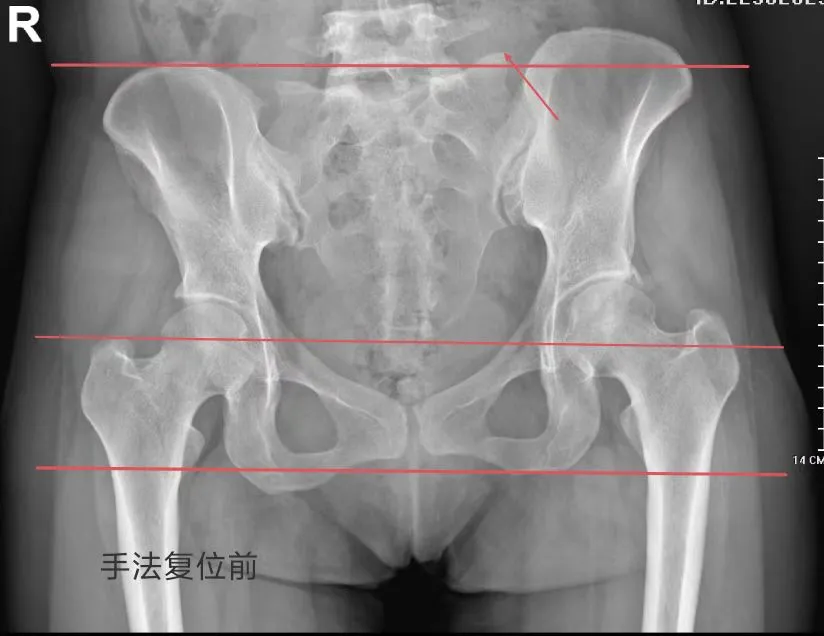

根据李女士的症状,妇产科医生黄素兰为她安排了骨盆X光片,结果发现,李女士的骨盆无骨折征象,耻骨联合分离6mm,属于正常范围内(耻骨联合分离:非妊娠骨盆正常值≤3mm,妊娠骨盆正常值7-9mm),但存在左侧骨盆向后旋转、右侧骨盆向前旋转,左侧髂骨、坐骨上移,右侧髂骨、坐骨下移的情况。

(修复前骨盆)